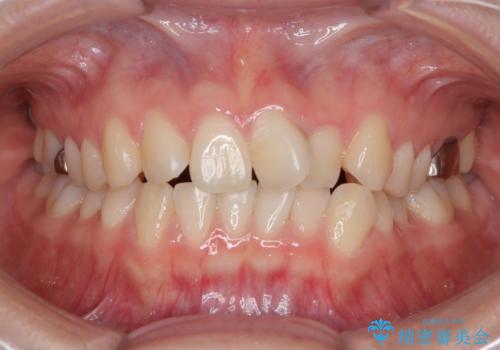

- 「前歯のねじれを改善したい」とのご希望で当院に来院された患者様です。

診察の結果、上下の前歯部に**叢生(そうせい/歯のガタガタ・重なり)**が認められました。

特に上の前歯にはねじれや重なりがあり、審美的にも清掃性にも影響している状態でした。

また、上顎前歯の重なっていた部分にはむし歯が見つかり、治療中に適切な処置を行っています。